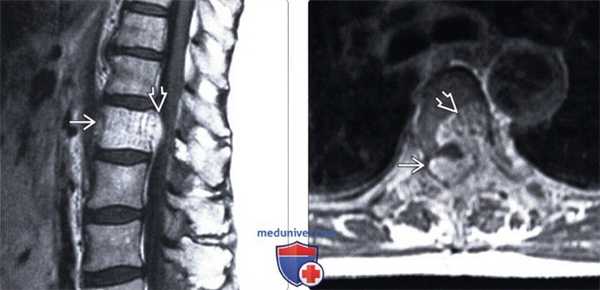

(Слева) На аксиальной МРТ (Т1 ВИ) определяются признаки агрессивной гемангиомы грудного позвонка с распространением в задние отделы и эпидуральное пространство. Жир визуализируется лишь в одной области. Точечный рисунок обусловлен трабекулами в гемангиоме.

(Справа) На сагиттальной МРТ (Т2 ВИ) визуализируется агрессивная гемангиома с гиперинтенсивным сигналом и легко различимым крупным эпидуральным компонентом. Видны также другие гемангиомы.